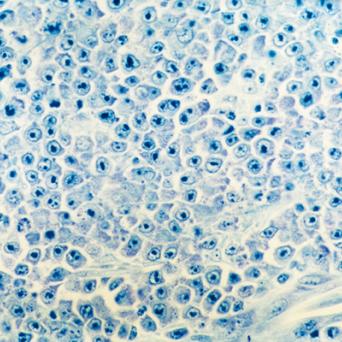

La stéatopathie métabolique est devenue la première cause de maladie chronique du foie. Le risque principal est la fibrose, qui, lorsqu’elle est sévère, peut évoluer vers une cirrhose et un carcinome hépatocellulaire. Qui faut-il dépister en soins primaires et comment interpréter les résultats ? Quelles options thérapeutiques ont fait leurs preuves ? Que peut-on attendre des nouvelles molécules ? Le point avec le Pr Stanislas Pol, hépatologue, hôpital Cochin, Paris.